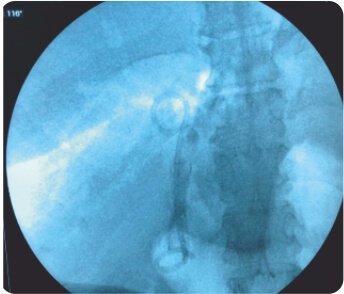

CBD এর EUS নির্দেশিত পাংচার ডুডেনামের প্রথম অংশ থেকে করা হয়েছিল। কোল্যাঞ্জিওগ্রামের পরে, ট্র্যাক্টটি সিস্টোটোম দিয়ে ক্রমান্বয়ে 10 ফারেনহাইট পর্যন্ত প্রসারিত করা হয়েছিল এবং একটি 60x10 মিমি সম্পূর্ণ আচ্ছাদিত বিলিয়ারি স্টেন্ট স্থাপন করা হয়েছিল যা D1 এবং CBD এর সাথে সংযোগ স্থাপন করে। একটি 7F 7cm ডবল পিগটেল প্লাস্টিক বিলিয়ারি স্টেন্ট মেটাল স্টেন্টের মধ্যে স্থাপন করা হয়েছিল যাতে এর স্থানচ্যুতি রোধ করা হয়। কোন পেরিপ্রোসিডারাল জটিলতা ছিল না। এক সপ্তাহের মধ্যে তার বিলিরুবিন স্বাভাবিক হয়ে যায় এবং তাকে কেমোথেরাপি করা হয়।

CBD এবং cholangiogram এর EUS নির্দেশিত পাংচার